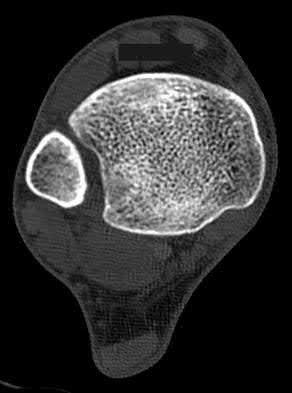

3. # Which of the following is not an appropriate implant for treatment of the fracture seen in Figure A?

5. Sliding hip screw Corrent answer: 5

The image shows a reverse obliquity intertrochanteric hip fracture.

According to the referenced article by Haidukewych et al, unstable peritrochanteric hip fractures have a worse outcome (failed in 9/16 cases) if treated with a sliding hip screw. Two additional factors that were found to have a strong correlation with postoperative failure (nonunion, loss of reduction) were poor reduction and poor implant placement. In this study, fixed angle devices were superior. Intramedullary fixation has the added advantage of a shorter lever arm and less potential for fracture collapse and limb shortening.

The IMN also acts as a medial buttress.

According to Sanders et al, the dynamic condylar screw (DCS) can also be used in subtrochanteric models, but should not be used if extensive comminution is seen, as they reported a high failure rate with DCS in these fractures if highly comminuted. They report a 77% overall union rate with this device.